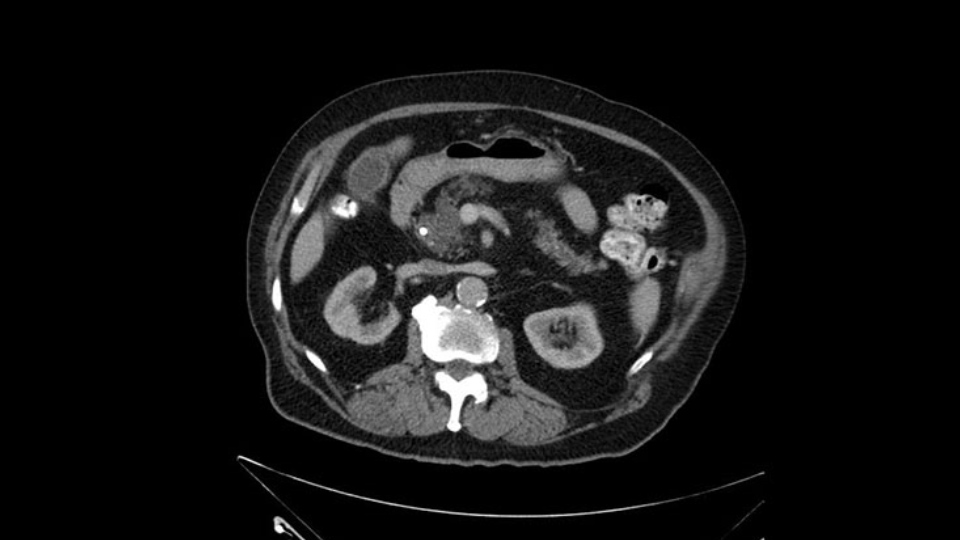

The only difference with him is that he has fairly extensive cystic lesions throughout his pancreas, particularly in the head and the neck. We have thought how this might affect the procedure. Likely IPMN (Intraductal Papillary Mucinous Neoplasms), and we have thought how this might affect the procedure. Is this a pancreatic adenocarcinoma rather than an ampullary cancer? The ampulla (of Vater) was abnormal on a side-viewing scope and a biopsy of this ampulla was adenocarcinoma. So I don’t think this was just a mass invading into the duodenum.

Number two, the reason why I think this IPMN might affect the procedure: it is involving the neck. So normally when we come across the neck, we would like to see a normal pancreas with a small or a large duct but you can see on the scan that this is fairly extensive duct and cystic lesion at that point. The only slowing down moment for me is really that. Coming across the pancreas, then wanting to see what that looks like and how that is going to affect my anastomosis.

I see a dilated biliary system but I also see a dilated pancreatic ductal system which is almost looking cystic in the head and neck region of the body. When I tackle the neck of the pancreas during the course of the surgery, I would have to pay particular attention to the neck of the pancreas when I transect it, to see for any changes of associated IPMN. They may not be IPMN but the thing is there is dilatation and that’s why I need to be careful, with the consideration for intraoperative frozen section for the pancreatic neck margin.

When reviewing the images of this patient, it is striking that there is a large dilation of the Wirsung duct, which is unusual in patients with carcinoma of the ampulla of Vater, and the dilatation in the head of the pancreas has almost replaced all the parenchyma, therefore there is a significant suspicion that the patient has an intraductal papillary mucinous tumor of the pancreas. It’s possible that it's a result of the same pathology and what we are seeing at the ampulla of Vater is the protrusion - because the pancreatic ducts are full of mucus; but we have a biopsy of adenocarcinoma, which could be a malignant degeneration, of an intraductal papillary mucinous tumor or a coincidence pathology, in addition to adenocarcinoma of the ampulla of Vater. Either way, if this patient is having surgery, the decision would be a pancreatoduodenectomy, But we should consider the possibility that the patient might have a intraductal papillary mucinous tumor of the pancreas.

There is a bit of a challenge in my mind that will have to be determined intraoperatively and that's the extent of the pancreatic duct dilatation as you move from the head of the gland more distally into the body and tail. We certainly can see dilatation of the pancreatic duct in patients with ampullary carcinoma. But this seems a little bit unusual in terms of the extended dilatation. It also stops pretty dramatically at the body of the gland with the dilatation not extending to the tail. So again, raises the suspicion that this could be a main duct IPMN. The patient would not require any further preoperative imaging. I don't believe an endoscopic ultrasound is going to add anything to this patient's management. So I would take the patient to the operating room at this time. I would not perform a diagnostic laparoscopy, that's not my practice even for pancreatic cancers at least involving the head of the gland.

After dividing the GDA you're really at the neck of the pancreas and in this case this is where the intraoperative decision making may be a little bit more challenging because as I mentioned, there's dilatation of the pancreatic duct well beyond the normal place where you would divide the pancreatic neck in a standard Whipple. So we would have to mobilize the patient further to the left, probably up to almost to the celiac axis or maybe even beyond as I look at this, it extends almost a centimeter or so into the splenic artery. You could take your chances on this, you could divide it and then do an intraoperative frozen section and at the time of intraoperative frozen section. If the pathologist says yes they see a main duct IPMN in the in the frozen section then I certainly would extend this further to the left until I was able to get far enough and back to normal pancreas. If this is normal ductal epithelium and the patient has a dilatation the pancreatic duct secondary to the ampullary obstruction, you could certainly make the operation technically easier by not extending that far to the left and be left with a generous pancreatic duct for your reconstruction. But I do think in this case, frozen section confirmation that you do not have a main duct IPMN will be essential to determine the extent of resection. I see no reason why this patient would be advised that they're going to need a total pancreatectomy. He does have a generous amount of gland in the body and tail but it will increase the technical difficulty of both resection and reconstruction to get to the left of where that dilatation ends.